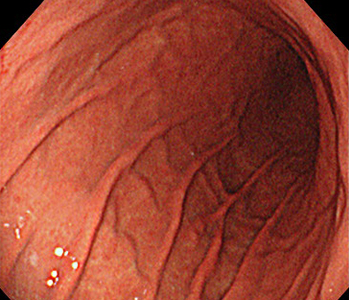

胃内視鏡(胃カメラ)画像

| ◆ 経口内視鏡(高解像度)◆ | ◆ 経鼻内視鏡 ◆ |

| 幽門 | 幽門(経鼻) |

※ 経鼻内視鏡はカメラの径が細いぶん、解像度が低く暗い画像となり病変の見逃しが多くなる傾向があります。